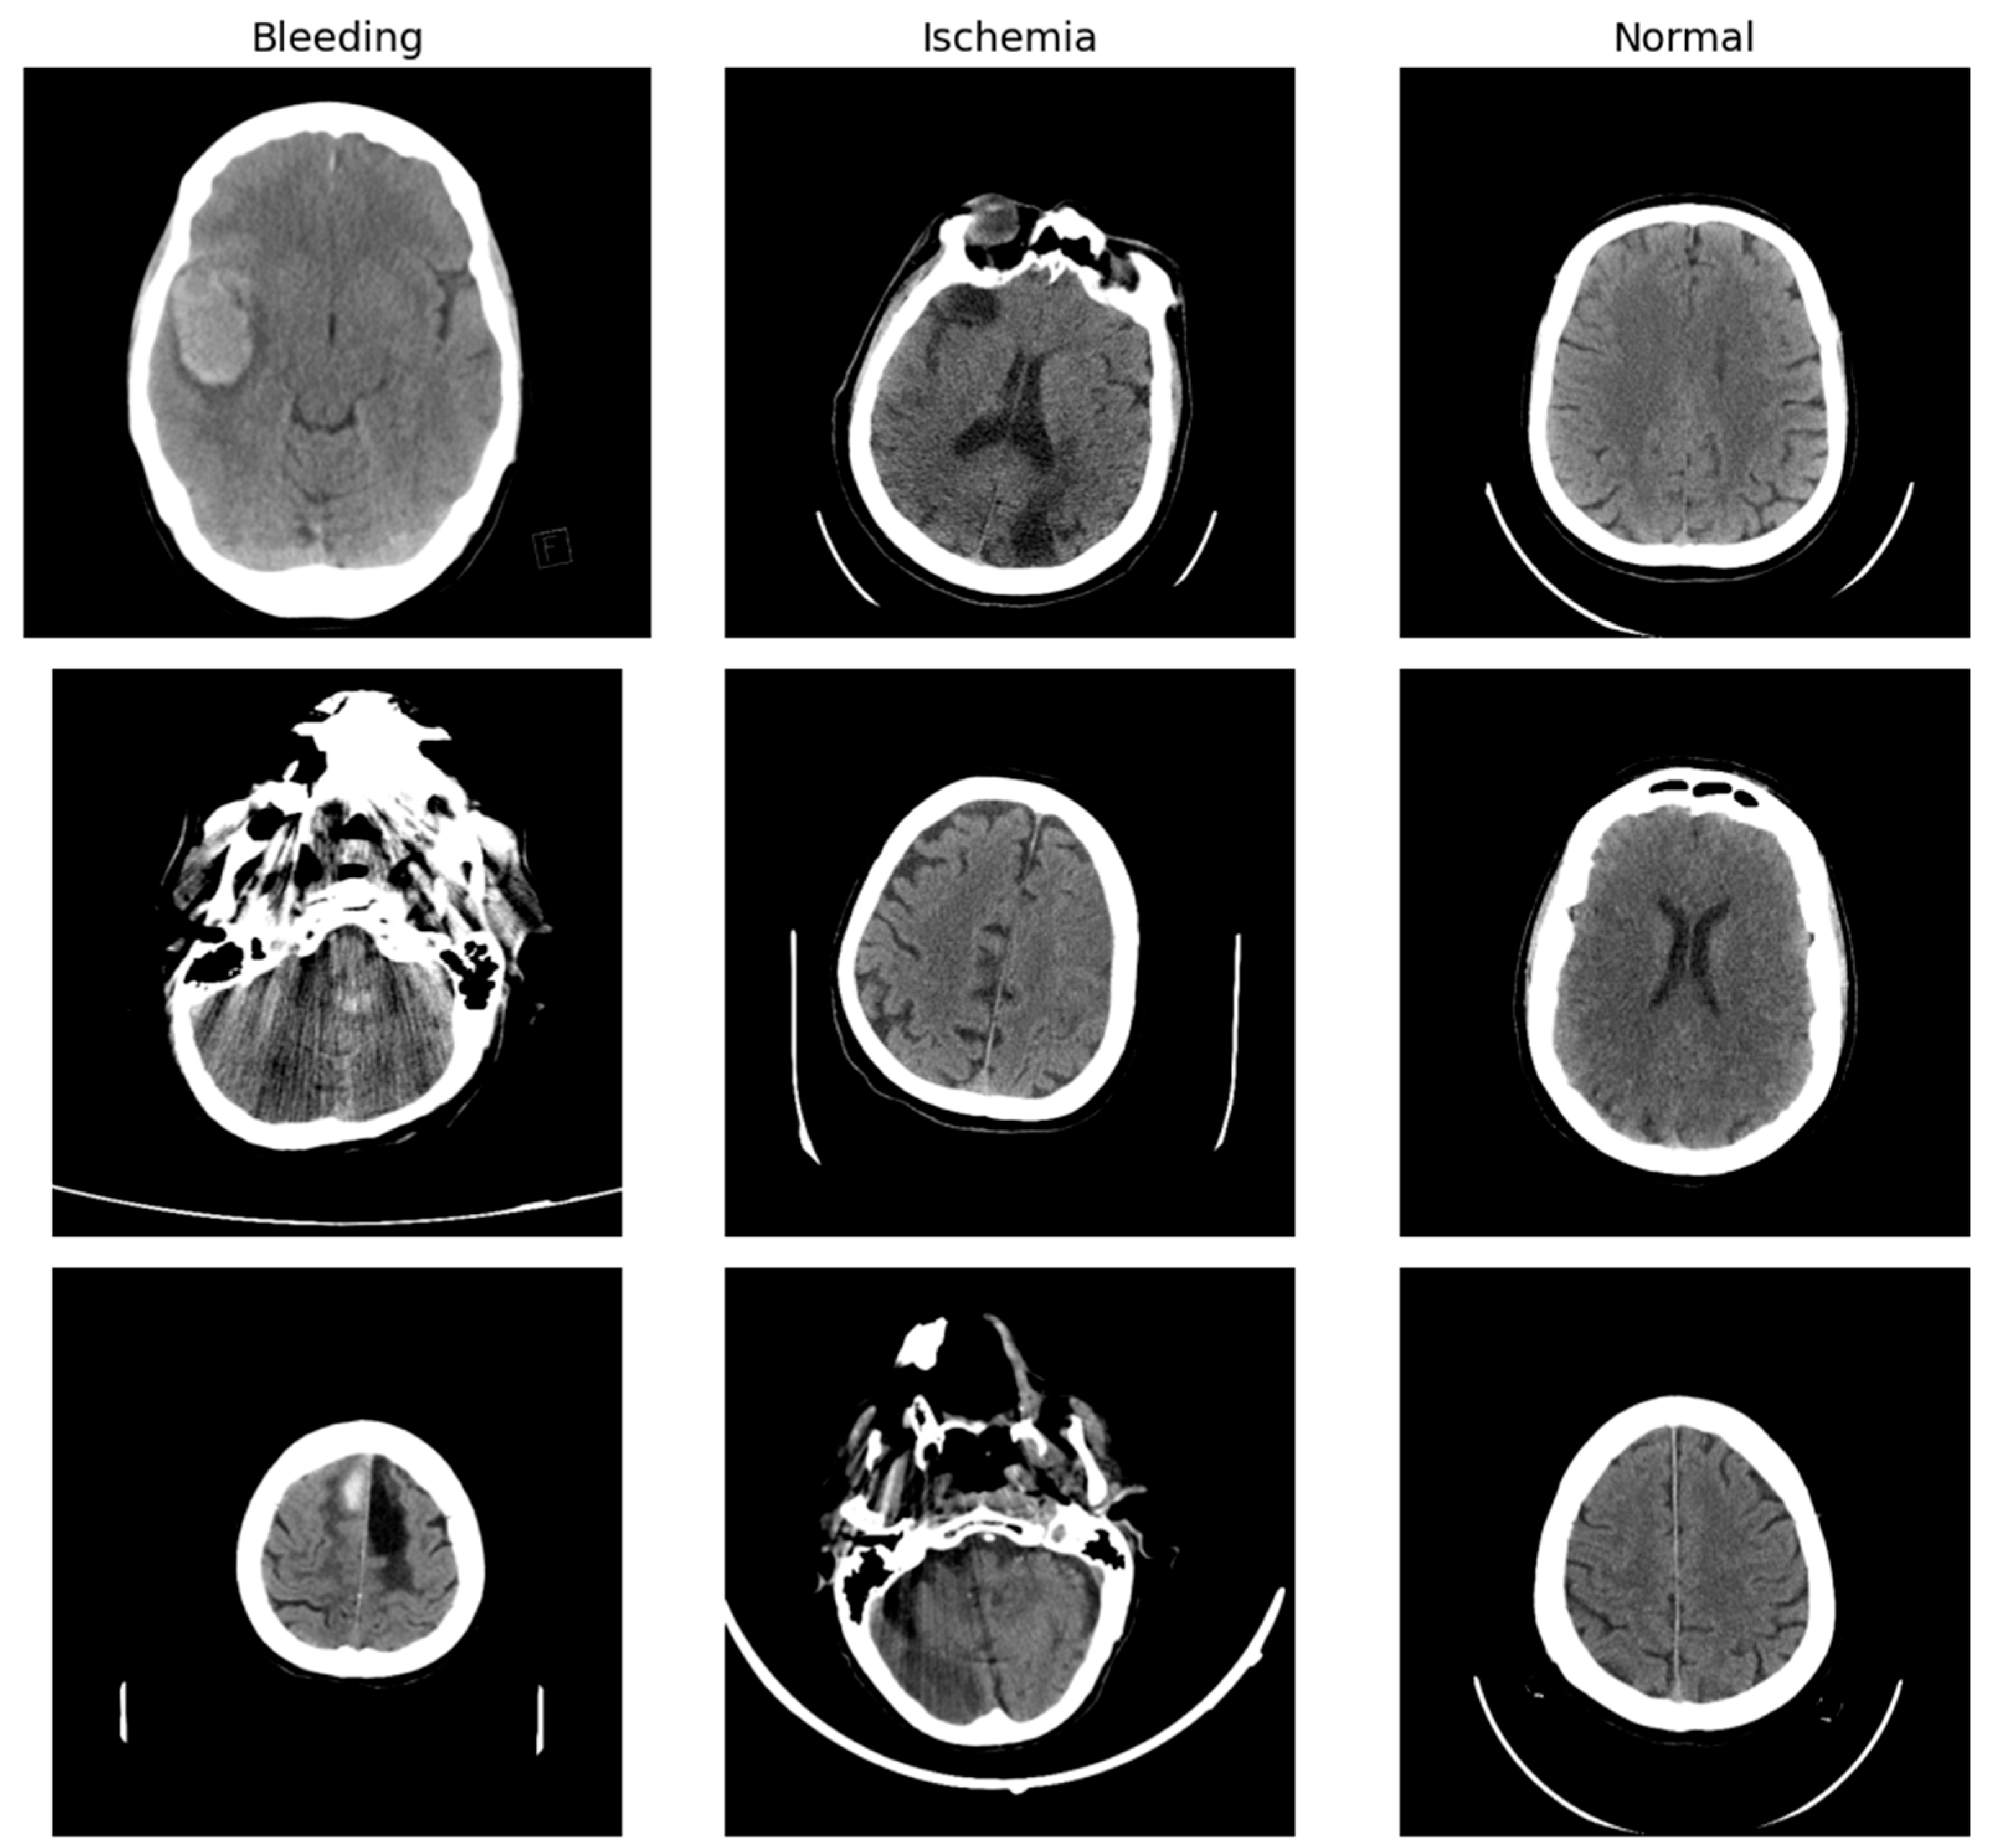

Each CT scan slice in the dataset is labeled with one of three diagnostic categories: normal (indicating no evidence of stroke), ischemic stroke, or hemorrhagic stroke due to intracranial bleeding. Among the 6653 images, 4428 are labeled as normal, 1131 as ischemic stroke, and 1094 as hemorrhagic stroke (Figure 1). This relatively imbalanced distribution, especially the predominance of normal scans, reflects the clinical reality in emergency radiology where non-stroke cases are common among individuals presenting with neurological symptoms. The dataset is hosted openly by the Turkish Ministry of Health and is cited with its publication in the Eurasian Journal of Medicine [17].

Figure 1. Sample Images per Class of Stroke.